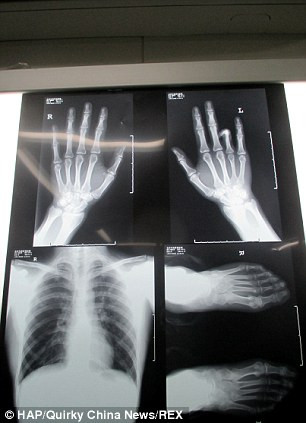

TPO - Lo sợ khó xin việc vì bị mất ngón tay áp úp bên trái trong một tai nạn hồi nhỏ, Ha Yuan, 22 tuổi đã nhờ các bác sỹ ghép ngón chân vào bàn tay.

Ngón chân được ghép thay thế cho ngón áp úp của tay trái

Các bác sỹ phẫu thuật ở tỉnh Hồ Nam, Trung Quốc đã cố gắng tách ngón chân trỏ trái, dùng nó thay thế cho ngón áp úp bị mất của cậu.

Bác sỹ Lu, người thực hiện phẫu thuật cho biết: “Rất khó để nhận ra sự khác biệt nếu thoạt nhìn qua. Điểm khác biệt duy nhất đó là kích thước móng”.

Ông Lu cũng cho biết thêm, phải mất 3 tháng để “ngón tay” mới này phục hồi chức năng.